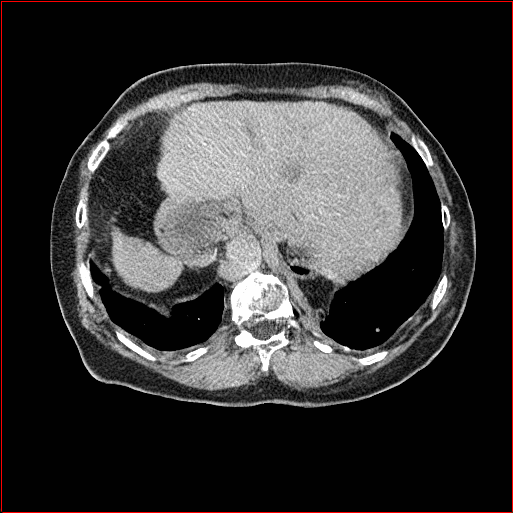

Panc. Tumor

1×1×11\times 1\times 1

mm

512×512×512512\times 512\times 512

Figure 4: MAISI-v2 segmentation-guided results for five types of tumors. We show results for different voxel spacing and volume size to demonstrate the flexibility of MAISI-v2. Different Hounsfield Unit window is used to better show the contrast between tumor and normal tissues.